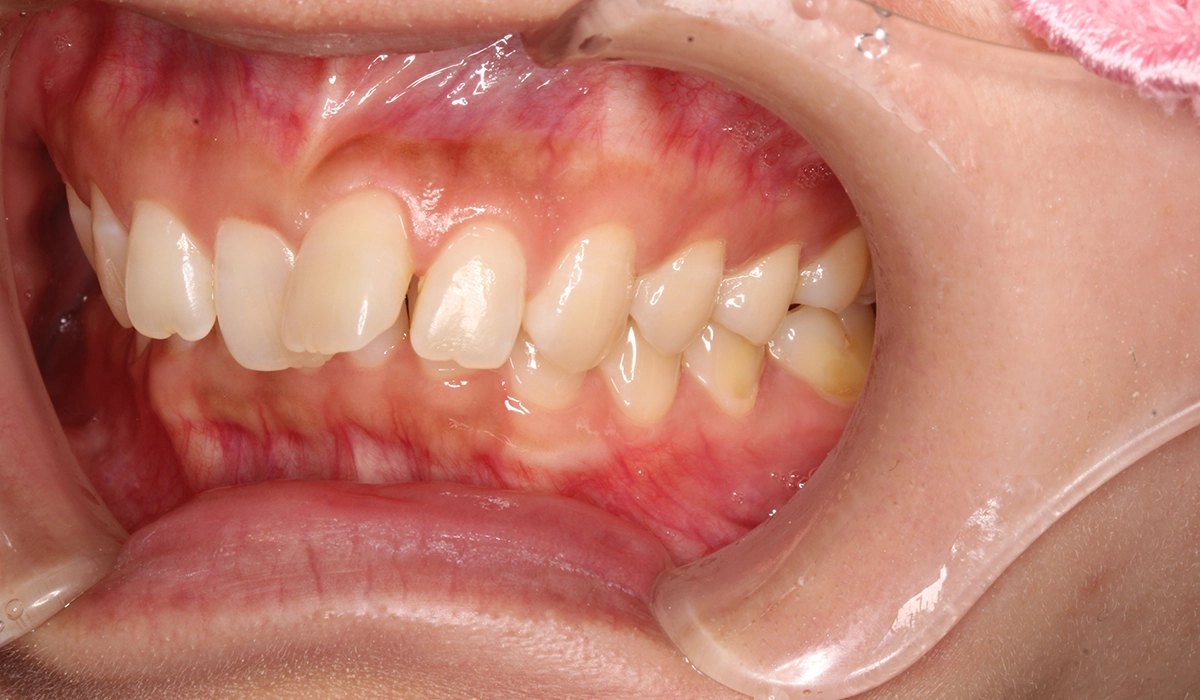

術前:右側

術後:右側